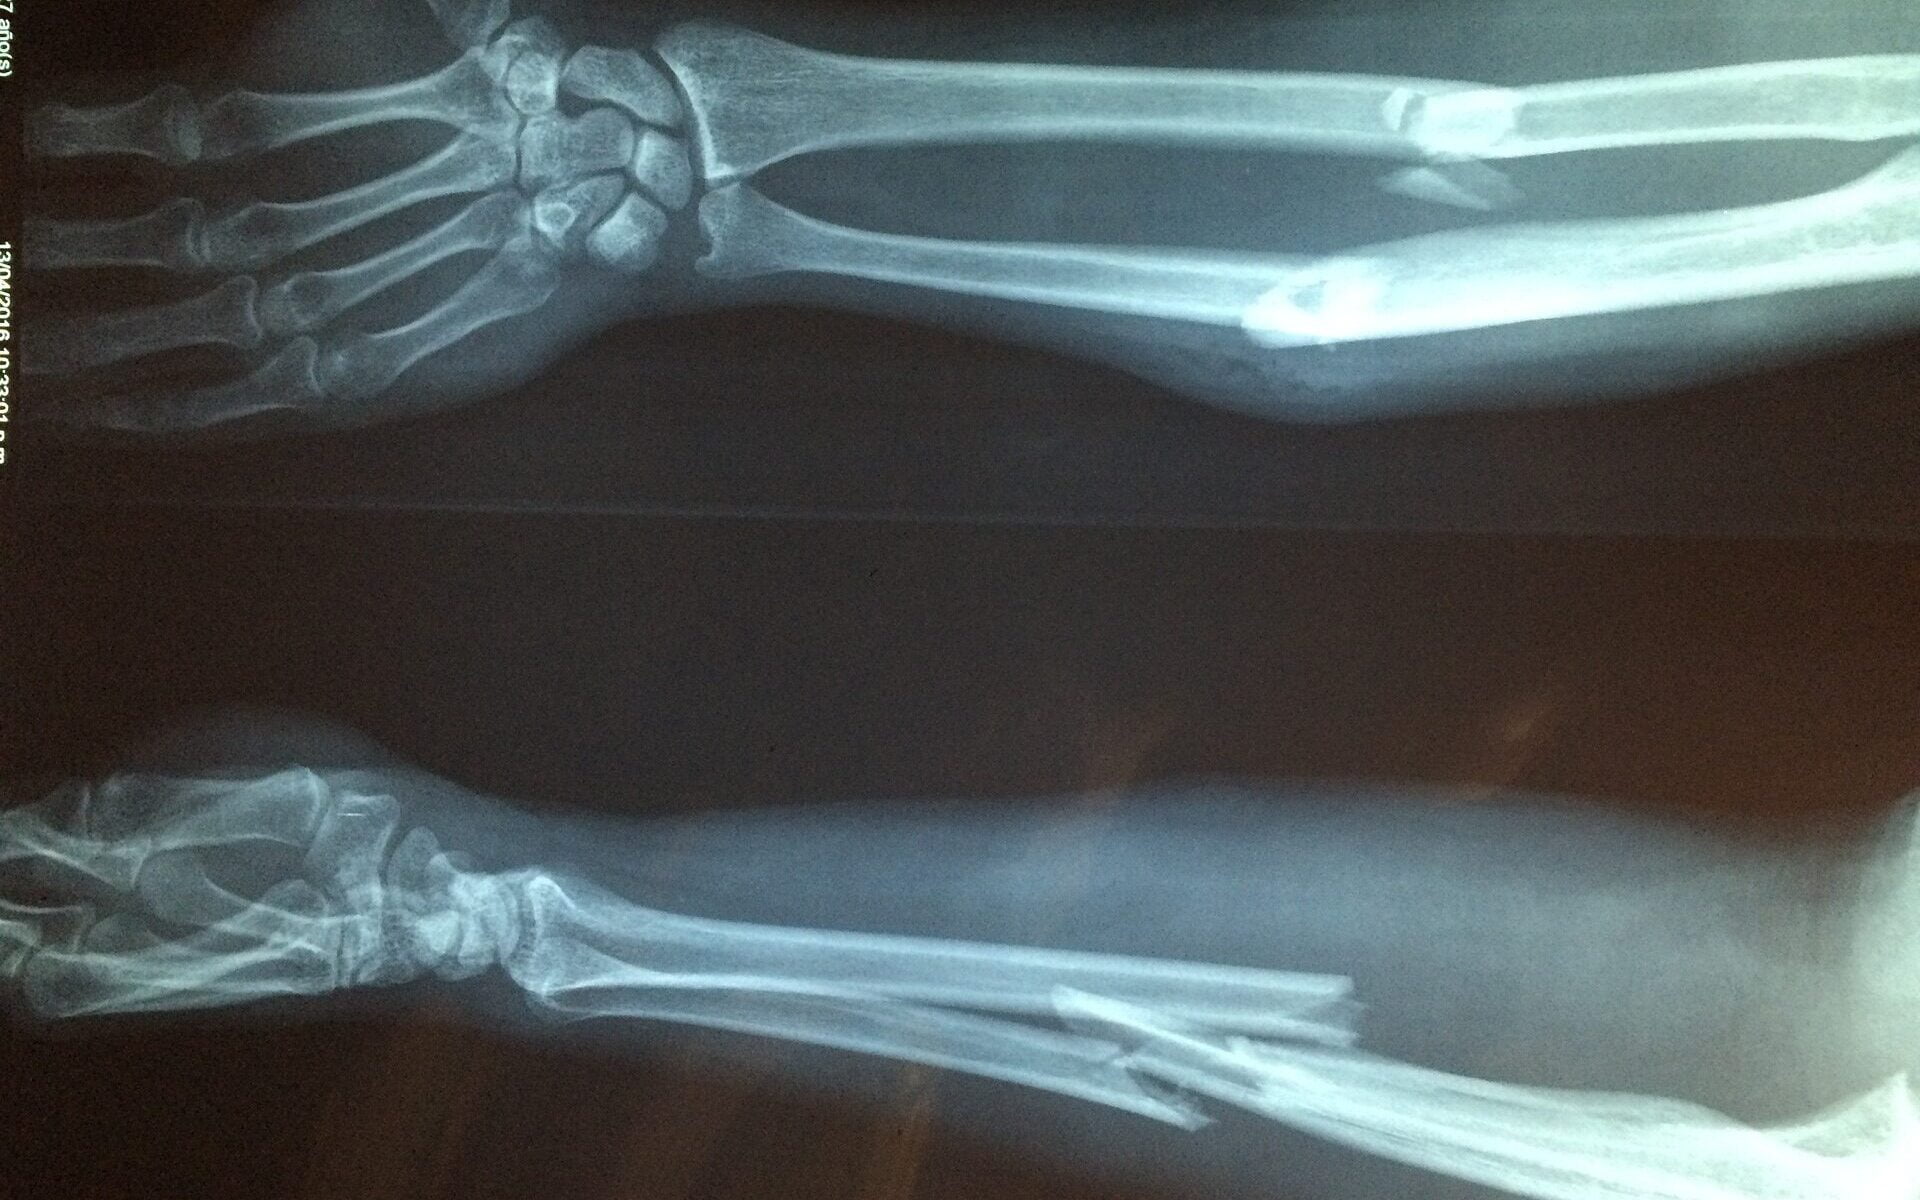

Reponointi tarkoittaa murtuneen tai sijoiltaan menneen eli luksoituneen raajan asettamista paikoilleen. Tietyissä tilanteissa ensihoitaja voi reponoida potilaan murtuneen tai luksoituneen raajan. Tällöin potilas kipulääkitään ja vedetään luksoitunut raaja paikalleen tai murtunut raaja sijoilleen niin, että poikki menneet luut olisivat mahdollisimman lähellä luonnollista asentoa.

Tyypillisiä tilanteita, joissa raaja reponoidaan, on esimerkiksi olkapään sijoiltaan meno potilailla, joilla on taipumus olkapään sijoiltaan menemiselle. Tavanomainen tilanne on urheillessa voimakas ja laaja käden liike, esimerkiksi tennismailaa heilauttaessa tai kaatuessa, jolloin kädellä otetaan maa vastaan.

Murtuneita raajoja reponoidaan kivun lievityksen ja lisävammojen ehkäisemiseksi. Pahasti virheasennossa oleva murtunut raaja voi painaa kivuliaasti potilaan kudoksia tai estää verenkierron raajan ääriosaan, jolloin reponointi kannattaa suorittaa jo kentällä. Kaikissa tilanteissa ei raajaa reponoida, koska joissain tilanteissa reponointi voi aiheuttaa lisävammoja.